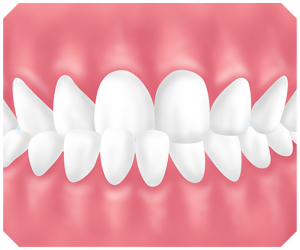

④過蓋咬合

過蓋咬合とは噛み合わせが深い状態をいいます。上の前歯が被さり下の前歯が見えない噛み合わせです。

原因は遺伝的なもの・歯の生え変わりがうまくいかなかった・強い力で噛み締めるなどです。

⑤交叉咬合

交叉咬合とは奥歯の噛み合わせが上下反対に噛んでいる状態のことです。

原因は永久歯が生える際にもともとの生える位置が悪く交叉してしまう場合と、いつも同じ側に頬杖をつくなどの外力によるものになります。

⑥開口

開口とは奥歯は噛み合っているにもかかわらず、上と下の前歯が噛み合ってない状態をいいます。原因は幼少期の指しゃぶりや舌を出す癖・口呼吸などです。

また、遺伝などで骨格的に問題があり、下あごの成長が悪い人はなりやすい傾向があります。

開口は、前歯で食べ物を咬み切ることができないばかりでなく、聞きとりにくい不明瞭な発音となってしまうなどの問題があります。